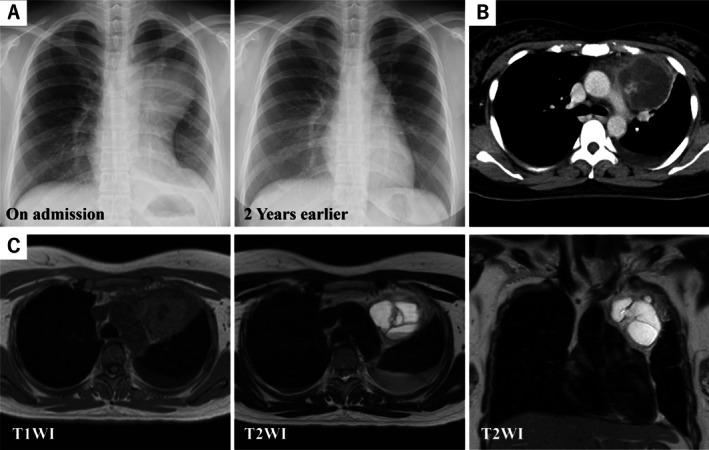

纵隔畸胎瘤表现为单向胰腺分化是非常罕见的。我们描述了一位36岁的女性,她的前胸痛逐渐恶化。计算机断层显示前纵隔一个5.9厘米的多室囊性肿块,伴胸膜和心包积液。考虑到病变的大小和推测的炎症反应,我们通过半壳切口进行根治性切除。组织病理学显示主要是胰腺腺泡组织和分散的非胰腺上皮成分,提示重新分类为纵隔畸胎瘤而不是异位胰腺。局灶性上皮破坏被认为是周围炎症的病灶。病人的术后过程平安无事。本报告强调了将畸胎瘤纳入前纵隔病变鉴别诊断的必要性,该病变最初被解释为异位胰腺,并说明了当存在广泛的局部粘连时,半壳入路实现完全、无伤性切除的价值。

Mediastinal teratomas demonstrating unidirectional pancreatic differentiation are exceedingly rare. We describe a 36-year-old woman with progressively worsening anterior chest pain. Computed tomography demonstrated a 5.9 cm multilocular cystic mass in the anterior mediastinum, accompanied by pleural and pericardial effusions. Given the lesion's size and presumed inflammatory reaction, we performed radical excision via a hemiclamshell incision. Histopathology revealed predominantly pancreatic acinar tissue with scattered non-pancreatic epithelial elements, prompting reclassification as a mediastinal teratoma rather than ectopic pancreas. Focal epithelial disruption was regarded as the nidus of the surrounding inflammation. The patient's postoperative course was uneventful. This report underscores the need to include teratoma in the differential diagnosis of anterior mediastinal lesions initially interpreted as ectopic pancreas and illustrates the value of the hemiclamshell approach for achieving complete, atraumatic resection when extensive local adhesions are present.